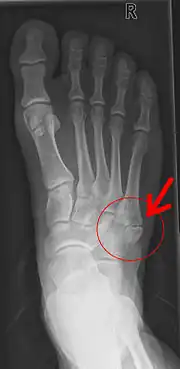

Pseudarthrose de la base du 5e métatarsien après un arrachement osseux.

Une pseudarthrose est une « fausse » articulation d'un os à l'endroit d'une fracture résultant de la cicatrisation indépendante des pièces de la fracture.

On parle plus précisément de pseudarthrose en cas de persistance du trait de fracture plus de 6 mois après la lésion initiale.